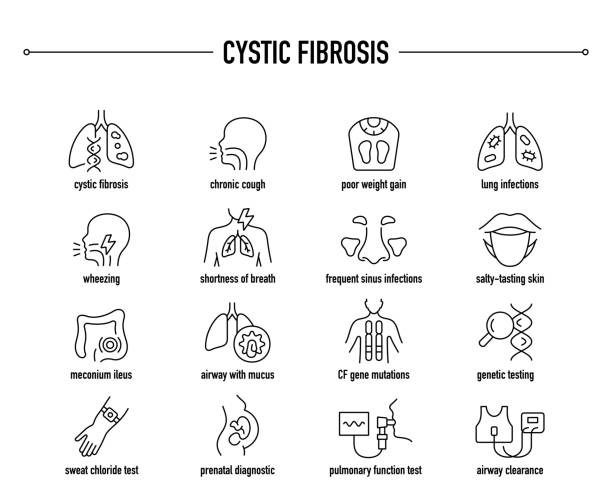

اعراض التليف الكيسي

تختلف أعراض التليف الكيسي باختلاف الشخص وشدة حالته، وعمره. قد تظهر الأعراض في الأطفال فى مرحلة الرضاعة، ولكن بالنسبة لبعض الأطفال، قد لا تبدأ الأعراض إلا بعد البلوغ أو حتى في مراحل لاحقة من العمر. ومع مرور الوقت، قد تتحسن الأعراض المصاحبة للمرض أو تسوء. يؤثر التليف الكيسي على الرئتين مسبباَ بعضا من الأعراض التنفسية مثل:

- صعوبة وضيق في التنفس.

- سعال مستمر قد يصاحبه مخاط أو دم.

- صفير أو أزيز أثناء التنفس.

يؤثر المخاط على الرئة ويعيق عملها لدى مرضى التليف الكَيسي ويمثل المخاط بيئةً مثاليةً لنمو مسببات الأمراض، ونتيجةً لذلك، يزداد خطر إصابة المريض بالتهابات الرئة، مثل التهاب الشعب الهوائية والالتهاب الرئوي.

تختلف أعراض التليف الكيسي من شخص لآخر، تبعًا للأعضاء المتضررة. ومن الأعراض والمضاعفات الأخرى التهابات الجيوب الأنفية المتكررة ومشاكل في الجهاز الهضمي، مثل:

- ألم في البطن.

- إمساك.

- براز دهني كريه الرائحة.

- زوائد لحمية أنفية.

- عرق شديد الملوحة، مما قد يترك بلورات صغيرة على الجلد يزيد التعرق فى المساء (تعرق ليلي).

- حمى.

- ألم في المفاصل والعضلات.

- انخفاض وزن الجسم بدون بذل جهد بالنسبة للبالغين.

- زيادة نسبة الصفراء في الجسم (اليرقان).

- عقم الذكور.

- تضخم أطراف الأصابع، نتيجة نقص الأكسجين في الأطراف.

- استدارة الأظافر.

طرق تشخيص التليف الكيسي

يتطلب تشخيص التليف الكيسي ظهور أعراض سريرية متوافقة مع أعراضه في جهاز عضوي واحد على الأقل، بالإضافة إلى دليل على خلل في وظيفة جين CFTR، ويتم عمل فحص قياس مستوى ملوحة العرق أو أخذ عينة دم أو تحليل جينى للتأكد من وجود طفرات في جين CFTR. لا يُشترط ظهور أعراض سريرية للرضع الذين يتم تشخيصهم من خلال فحص حديثي الولادة.

تشمل الفحوصات التشخيصية الأخرى التي قد تُجرى ما يلي:

- اختبار العرق (Sweat Test): يُعد من الفحوصات الأكثر شيوعًا لتشخيص التليف الكيسي، حيث يفحص ارتفاع مستوى الملح في العرق، حيث يتم وضع مادة كيميائية لتحفيز الجلد على التعرق عند تعرضه لتيار كهربائي ضعيف. يُجمع العرق على ضمادة أو ورقة، ثم يُحلل. يُشخص التليف الكيسي إذا كان العرق أكثر ملوحة من المعتاد.

- تحليل التربسينوجين المناعي (IRT): يُعدّ معياريًا لفحص حديثي الولادة، ويتم إجراؤه عن طريق أخذ عينة دم (قطرة دم من كعب الرضيع)، يتم تحليل عينة الدم لقياس مادة تسمى “التربسين المناعي المتفاعل” (IRT)، وإذا كانت المستويات مرتفعة، تجرى اختبارات إضافية (مثل اختبار العرق أو الاختبار الجيني) للتأكد من التشخيص.

- الاختبار الجيني (Genetic Test): حيث يتم أخذ عينة دم أو مسحة من باطن الخد لتحليل الحمض النووي (DNA) لتحديد الطفرات في جين CFTR، وهو الجين المسؤول عن المرض.

يتم أيضا عمل فحص الأجنة والحالات المشتبه بها واختبارات وظائف الرئة للتأكد من التشخيص وكذلك فحص عينات المخاط وتستخدم في التشخيص الأشعة السينية على الصدر والأشعة المقطعية.